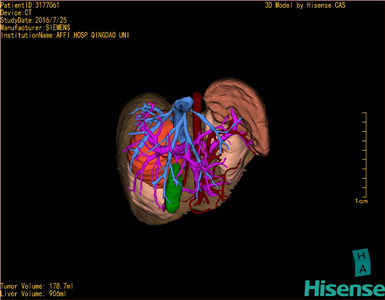

通过调节窗宽窗位调整CT序号,对肿瘤,肝实质,胆囊,下腔静脉,肿瘤,肝动脉、门静脉及肝静脉等进行三维重建;系统自动计算肿瘤体积和肝脏体积。

模拟手术操作,自动计算切除肿瘤体积。肝脏体积为906ml,肿瘤体积为178.7ml,肿瘤体积为肝脏体积的19.7%,通过比对6-9月正常肝脏体积为257.75±51.05ml,通过术前模拟手术,精准判断切除后剩余肝脏体积能耐受,避免肝衰竭发生。

术前三维重建: